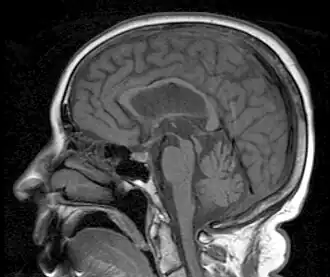

![]() Resonancia magnética que muestra el signo del colibrí de la parálisis supranuclear debido a la atrofia del mesencéfalo | ||